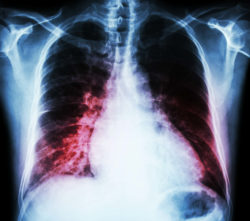

Some of the most common symptoms of heart failure that are explained in the Onglyza FDA warning include weakness, fatigue, unusual shortness of breath during typical activities, tiredness, trouble breathing when lying down, and weight gain with swelling in the legs, ankles, stomach or feet.

Those patients who took Onglyza were more likely to be hospitalized for heart failure than those who were using other medications. When the heart muscle becomes too weak to pump blood throughout the rest of the body, heart failure can occur. If this situation is not addressed immediately, the person who is affected by it may be at a higher risk of suffering fatal injuries.